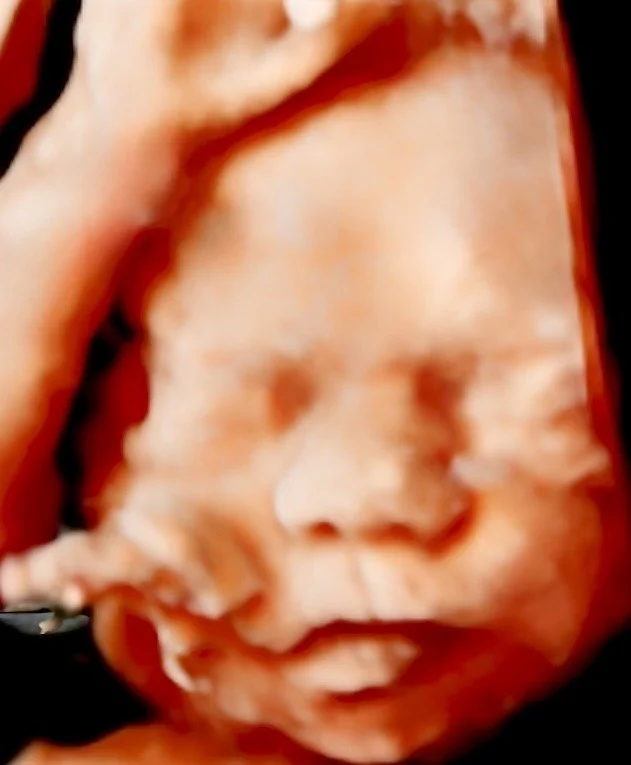

8K Ultrasound Images A Premium Upgrade to Your 3D Baby Ultrasound Our work speaks for itself — Our work speaks for itself — Our work speaks for itself —